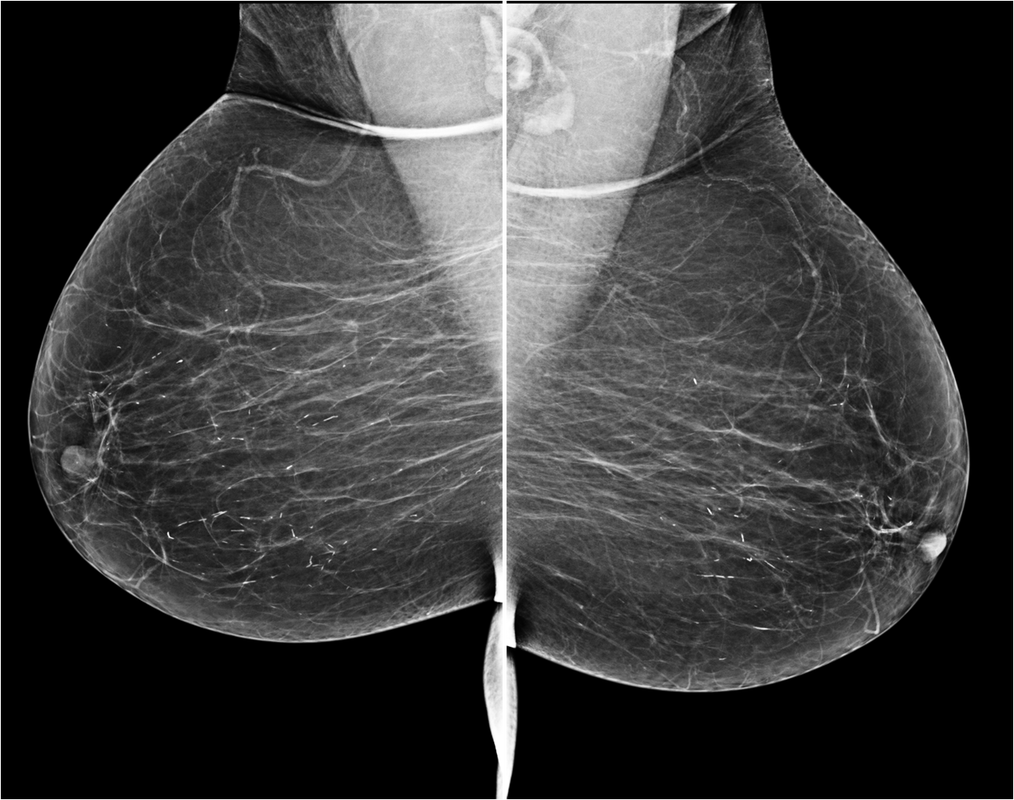

43 year female patient has come for routine screening mammogram...

Read More